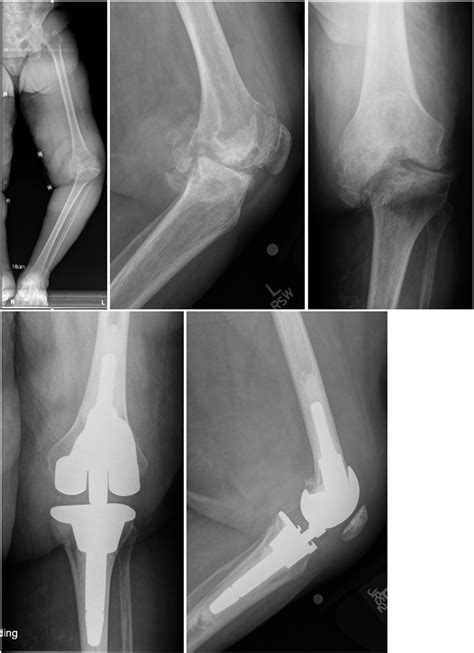

Complex Knee Injury – Thai Ortho Trauma Society (T.O.T.S.)

Evidence-Based Management of Complex Knee Injuries: Restoring the